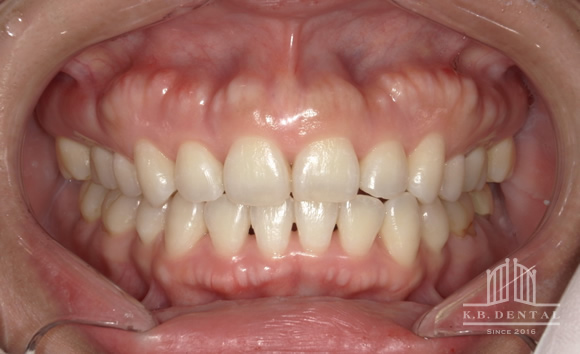

上顎外側骨隆起 症例1

咬合の応力は上顎の場合、必ずしも口蓋正中に集中するわけではありません。

歯列や歯牙の傾斜の角度により外側に分散することがあります。

その場合、上下とも外側に大きな骨隆起を生じます。

これが大きくなりすぎると食物残渣の停滞を引き起こし口腔内の不快感、口腔衛生状態の悪化につながります。

治療は外科的に除去することが第一選択肢となります。

静脈内鎮静法による麻酔代込:約17万円(保険適用外)